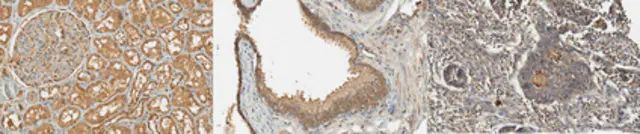

The Human Protein Atlas project can be subdivided into three efforts: Human Tissue Atlas, Cancer Atlas, and Human Cell Atlas. The antibodies that have been generated in support of the Tissue and Cancer Atlas projects have been tested by immunohistochemistry against hundreds of normal and disease tissues and through the recent efforts of the Human Cell Atlas project, many have been characterized by immunofluorescence to map the human proteome not only at the tissue level but now at the subcellular level. These images and the collection of this vast data set can be viewed on the Human Protein Atlas (HPA) site by clicking on the Image Gallery link. To view these protocols and other useful information about Prestige Antibodies and the HPA, visit sigma.com/prestige.

• IHC tissue array of 44 normal human tissues and 20 of the most common cancer type tissues.